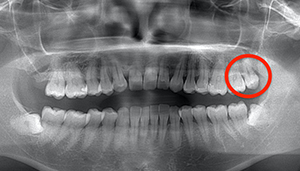

左下親知らずがたまに痛み、

できれば痛くなく抜きたい症例

- 抜歯前写真(レントゲン)

- 抜歯前写真(CT画像)

| 年齢 | 20代・女性 |

|---|---|

| 主訴 | 左下親知らずがたまに痛み、できれば痛くなく抜きたい |

| 親知らずの生え方 | 完全に埋まっている、横向きに生えている |

| 抜歯時間 | 50分 |

| 費用 | 約8,000円(保険診療、CT代含む) |

| 抜歯内容 | 左下親知らずが横向きになって半分埋まっている状態だったため、麻酔を行い、親知らずの奥の歯ぐきに切開をいれ、歯が囲んでいる骨を削り、歯の頭の部分を削って出し、その後根の部分に器具をかけて抜歯しました。 親知らずが一部神経に近い部分があったため、術後に麻痺が出る可能性がありました。このケースでは事前にCTを撮影し、歯の位置、根の方向、神経との距離を確認していたため、幸い麻痺が出ることはありませんでした。 術後1週間経過して糸取りをして治療は終了となりました。抜歯後3日間は腫れと痛みで大変だったが、糸取りをする頃には痛みも腫れも無くなったと患者さまも喜んでおられました。 |